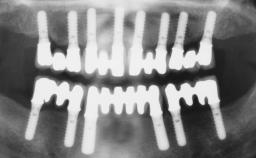

Iliac-Crest Block for Vertical and Horizontal Space Filling in the Anterior Maxilla

A 31-year-old man presented to our clinic 30 days after a motor vehicle accident in which he had suffered a dentoalveolar fracture in the anterior maxilla, including avulsion of teeth 12 and 11 and luxation of tooth 21. He was first treated on the night of the accident in a small city hospital with no oral and maxillofacial surgeon on the staff. A wired retention had been applied and the teeth repositioned to the best of the clinicians’ abilities. When he first presented to our care, the patient showed extrusion of teeth 12 and 11 associated with gingival recession due to bone loss in the anterior maxilla, and the stainless steel wires were still present.

Bone Augmentation Horizontal|Staged|Vertical

Augmentation Materials Autogenous chips|Autogenous block(s)

Bone Volume Deficient vertically or deficient vertically AND horizontally